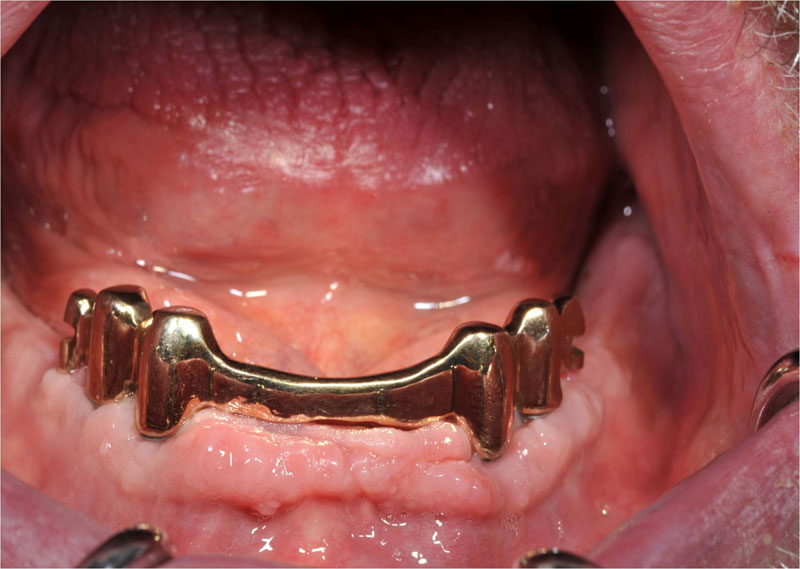

Unterkiefer Stegversorgung

| Hier bieten vier Implantate eine relativ einfache Möglichkeit eine Prothese mit zwei Riegeln optimal zu befestigen. Diese sind an der Prothese im geöffneten Zustand deutlich zu sehen, geschlossen bleiben sie selbst im Spiegelbild des Mundinnenraumes unsichtbar. Sie vergessen alle Druckstellen und Ängste und freuen sich endlich wieder einmal richtig abbeissen zu können! |